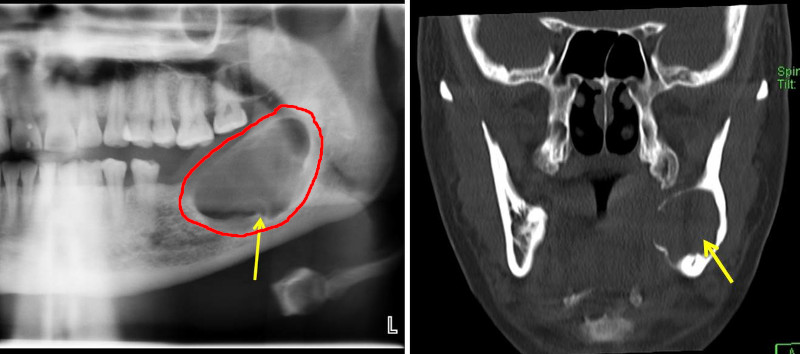

Ameloblastoma

- Descrizione: Tumore che compare nel mascellare (maggiormente nell'inferiore) distruggendo tanto la gengiva come l'osso.